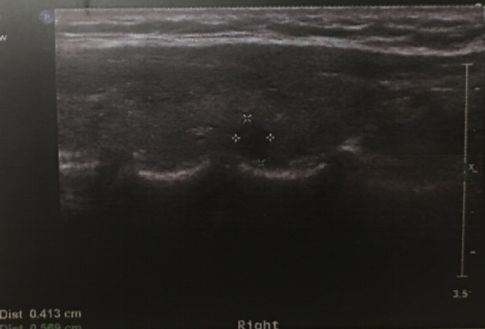

图:超声发现直径4mm的PTMC。

手术前诊断的金标准是细针穿刺活检(fine needle aspiration,FNA),但是对于肿瘤直径特别小(如小于5mm)的癌灶,可能并不适合穿刺,或者穿刺有假阴性可能或为意义不明确的结果。当超声检查发现典型的超声表现时,包括低回声、微钙化、纵横比大于1等,基本也可以诊断PTMC。临床诊断的建立同时要兼顾患者是否具有甲状腺癌的高危因素,如家族史,颈部放射史等。